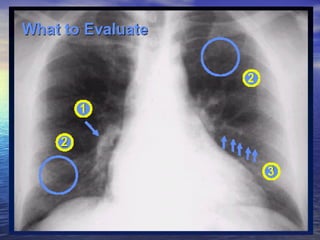

Main pulmonary artery big Normal Vasculature               Pulmonic stenosis                                      Idiopathic pulmonary artery dilatation               Hyperdynamic states  Increased flow (Left to right shunts)  ASD             VSD                                                           PDA                                                          Anomalous pulmonary venous return

Main pulmonary big (continued) Pulmonary venous hypertension                Presupposes left atrial enlargement  Pulmonary arterial hypertension  Lungs - normal             multiple pulmonary emboli, COPD ,  Lungs - abnormal Schistosomiasis